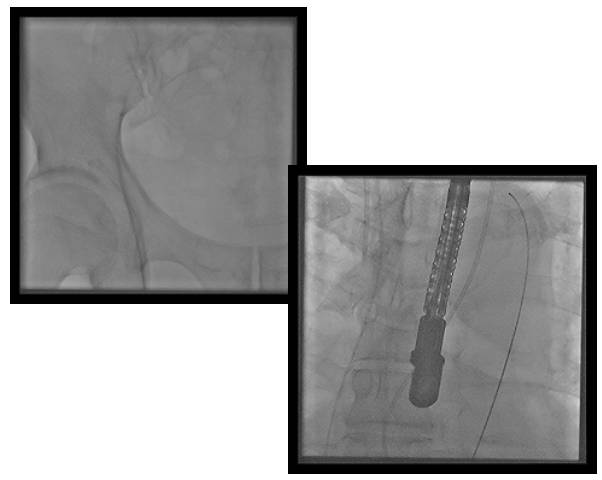

◆2015年1月17日行TAVI术。

◆植入29mm CoreValve人工支架瓣膜一枚。

术后症状明显缓解,近一年未因心衰住院;

一年期复查心超,未见主动脉瓣狭窄和关闭不全。